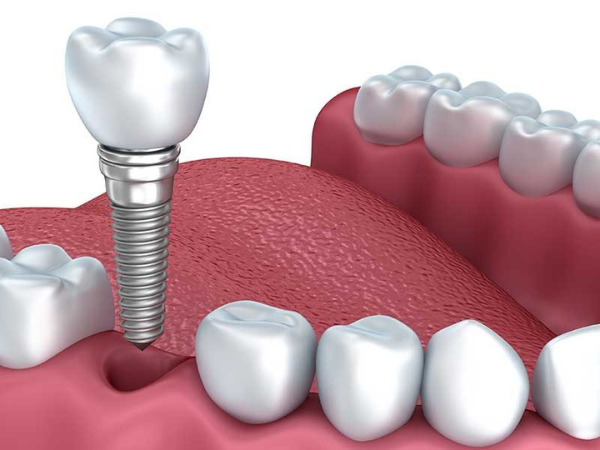

A ponte fixa sobre implante é indicado para pessoas que perderam alguns dentes intercalados ou da mesma região da boca. Realizar um tratamento com implante parcial é uma alternativa muito mais eficiente do que uma ponte convencional.

Os dentes presos em implantes dentais oferecem melhores resultados estéticos (não possui grampos metálicos) e dessa maneira impedem a reabsorção óssea.

Possibilita a sensação mais próxima possível de dentes naturais que a odontologia moderna oferece.

Os dentes vizinhos permanecem íntegros

Os dentes vizinhos permanecem íntegros